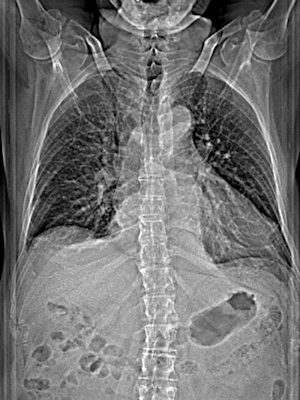

my lungs: were loaded with 6 litres of water in 2024, seriously affecting my heart.

Lunge

my lungs full of water

in March 2024